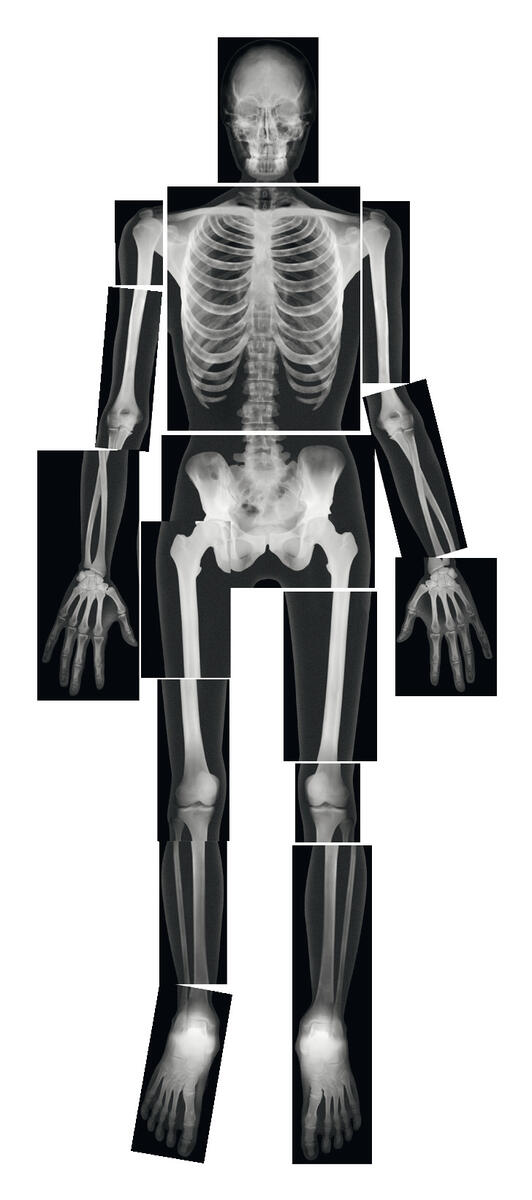

Röntgenbilder människoskelett

Sätt ihop 18 st bilder för att få ihop hela skelettet på en människa s...

Sätt ihop 18 st bilder för att få ihop hela skelettet på en människa som är 1,5 meter.